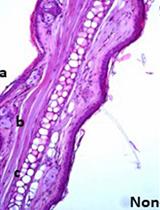

Outer membrane vesicles (OMVs) are spherical bilayered phospholipids of 20-200 nm in size produced from all Gram-negative bacteria and Gram-positive bacteria investigated to date. OMVs, which resemble the outer membrane and periplasm in composition, are proinflammatory and immunogenic facsimiles, and therefore could activate both innate and adaptive immunity. Here, we describe the OMVs immunization protocol and bacteria challenge protocol to induce bacterial sepsis in mice.